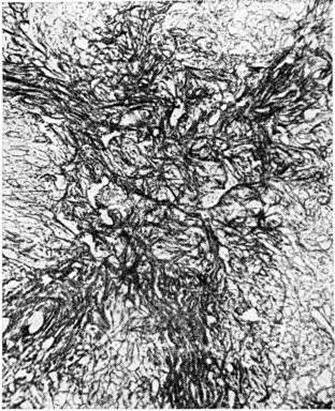

При микроскопическом исследовании в костном мозге преобладают незрелые и зрелые клетки гранулоцитарного ряда (рисунок 5), соотношение которых может варьировать. По данным трепанобиопсий, в начальной стадии заболевания ещё в достаточном количестве сохраняются элементы эритропоэтического и мегакариоцитарного ряда. По мере прогрессирования процесса их число снижается, исчезают жировые клетки. Характерны глубокие изменения в строме в виде сочетания процессов деструкции с увеличением количества фибробластов, аргирофильных и иногда коллагеновых волокон. Изучение костного мозга методом трепанобиопсии в динамике свидетельствует о том, что миелофиброз постепенно нарастает и бывает более выражен у больных с повторными ремиссиями и обострениями заболевания. В отдельных случаях в костном мозге имеют место обширные очаги некроза; постоянно наблюдается выраженное рассасывание костной ткани. В селезёнке и лимфатических узлах в развёрнутой стадии болезни обнаруживается диффузная инфильтрация миелоидными элементами, атрофия лимфатической ткани. Лейкозное поражение селезёнки часто сопровождается выраженным в различной степени фиброзом красной пульпы, образованием полей склероза, что наряду с инфильтрацией и полнокровием является причиной увеличения её веса. Для хронический миелолейкоза характерна локализация лейкозных инфильтратов в печени по ходу синусоидных капилляров (рисунок 6), в лёгких — в области межальвеолярных перегородок. Нередко наблюдается инфильтрация стенок мелких бронхов, сосудов, плевры. Реже, чем при острых Лейкозы очаги лейкозной инфильтрации возникают в почках, мышце сердца, в стенках желудочно-кишечные тракта, в оболочках и веществе головного мозга, коже, железах внутренней секреции и других органах.